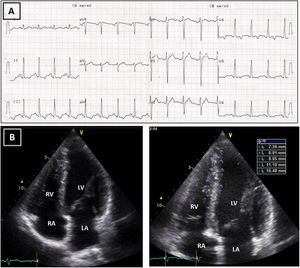

Resting electrocardiogram (ECG) (top) and transthoracic echocardiogram (TTE) (bottom), performed four months after detraining. (A) The ECG shows a clear improvement of the T-wave abnormalities in the inferior and lateral leads, although the ECG is still abnormal; (B) on TTE, a decrease in both septal and apical LV wall thickness is evident (maximum 11 mm). LA: left atrium; LV: left ventricle; RA: right atrium; RV: right ventricle.